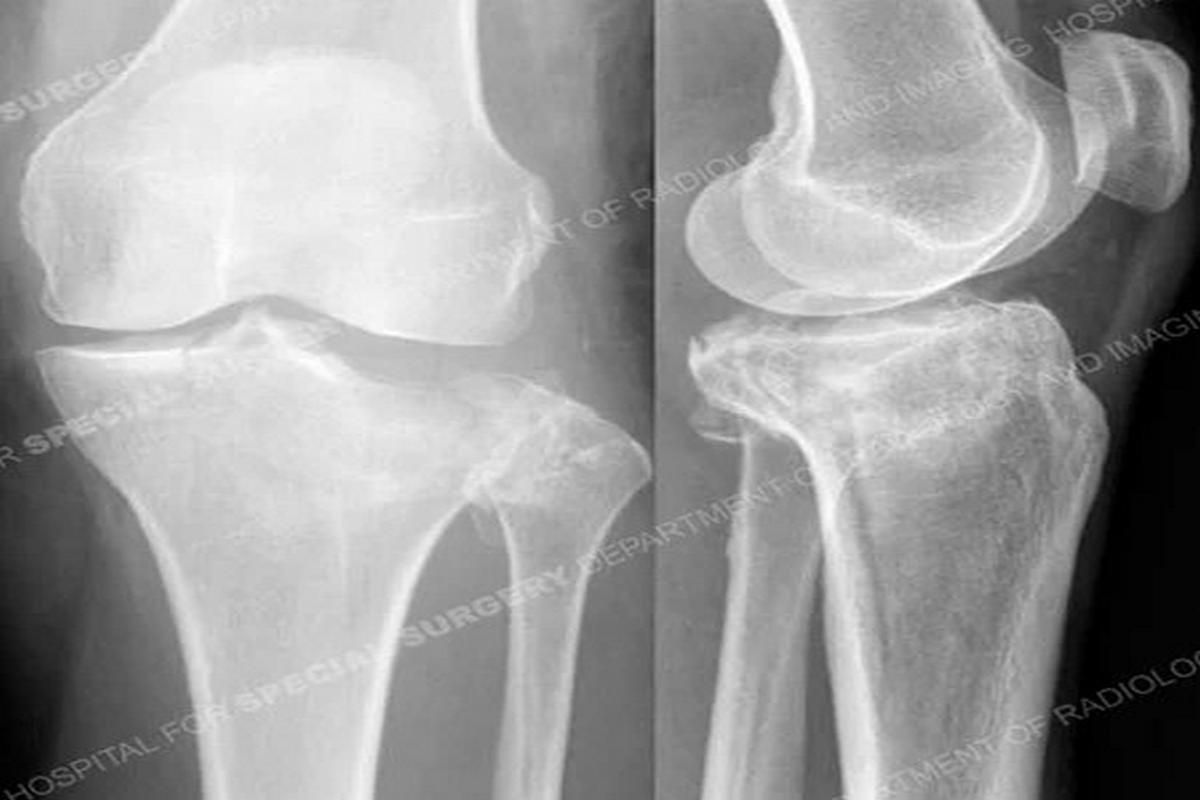

Διαϋπερκονδύλια κατάγματα μηριαίου

Τα διαϋπερκονδύλια κατάγματα εντοπίζονται στο κατώτερο άκρο του μηριαίου οστού, ακριβώς πάνω από την άρθρωση του γόνατος.

Συνήθως προκαλούνται από τραυματισμούς υψηλής ενέργειας, όπως τροχαία ατυχήματα ή πτώσεις από ύψος. Σε ηλικιωμένους ασθενείς με οστεοπόρωση, μπορεί να εμφανιστούν ακόμη και μετά από χαμηλής ενέργειας κάκωση.

Οι ασθενείς παρουσιάζουν έντονο πόνο, οίδημα, αδυναμία στήριξης του σκέλους και συχνά εμφανή παραμόρφωση. Η διάγνωση γίνεται με ακτινογραφίες, ενώ η αξονική τομογραφία είναι απαραίτητη για την ακριβή εκτίμηση της γραμμής και της πολυπλοκότητας του κατάγματος.

Η θεραπεία είναι κατά κανόνα χειρουργική και περιλαμβάνει οστεοσύνθεση με πλάκες και βίδες ή ενδομυελικούς ήλους, με στόχο την ανατομική ανάταξη και τη σταθερότητα. Συντηρητική αγωγή εφαρμόζεται σπάνια και μόνο σε ασθενείς που δεν μπορούν να υποβληθούν σε χειρουργείο.

Πιθανές επιπλοκές είναι η μη πώρωση, η δυσκαμψία του γόνατος και η ανάπτυξη μετατραυματικής αρθρίτιδας.